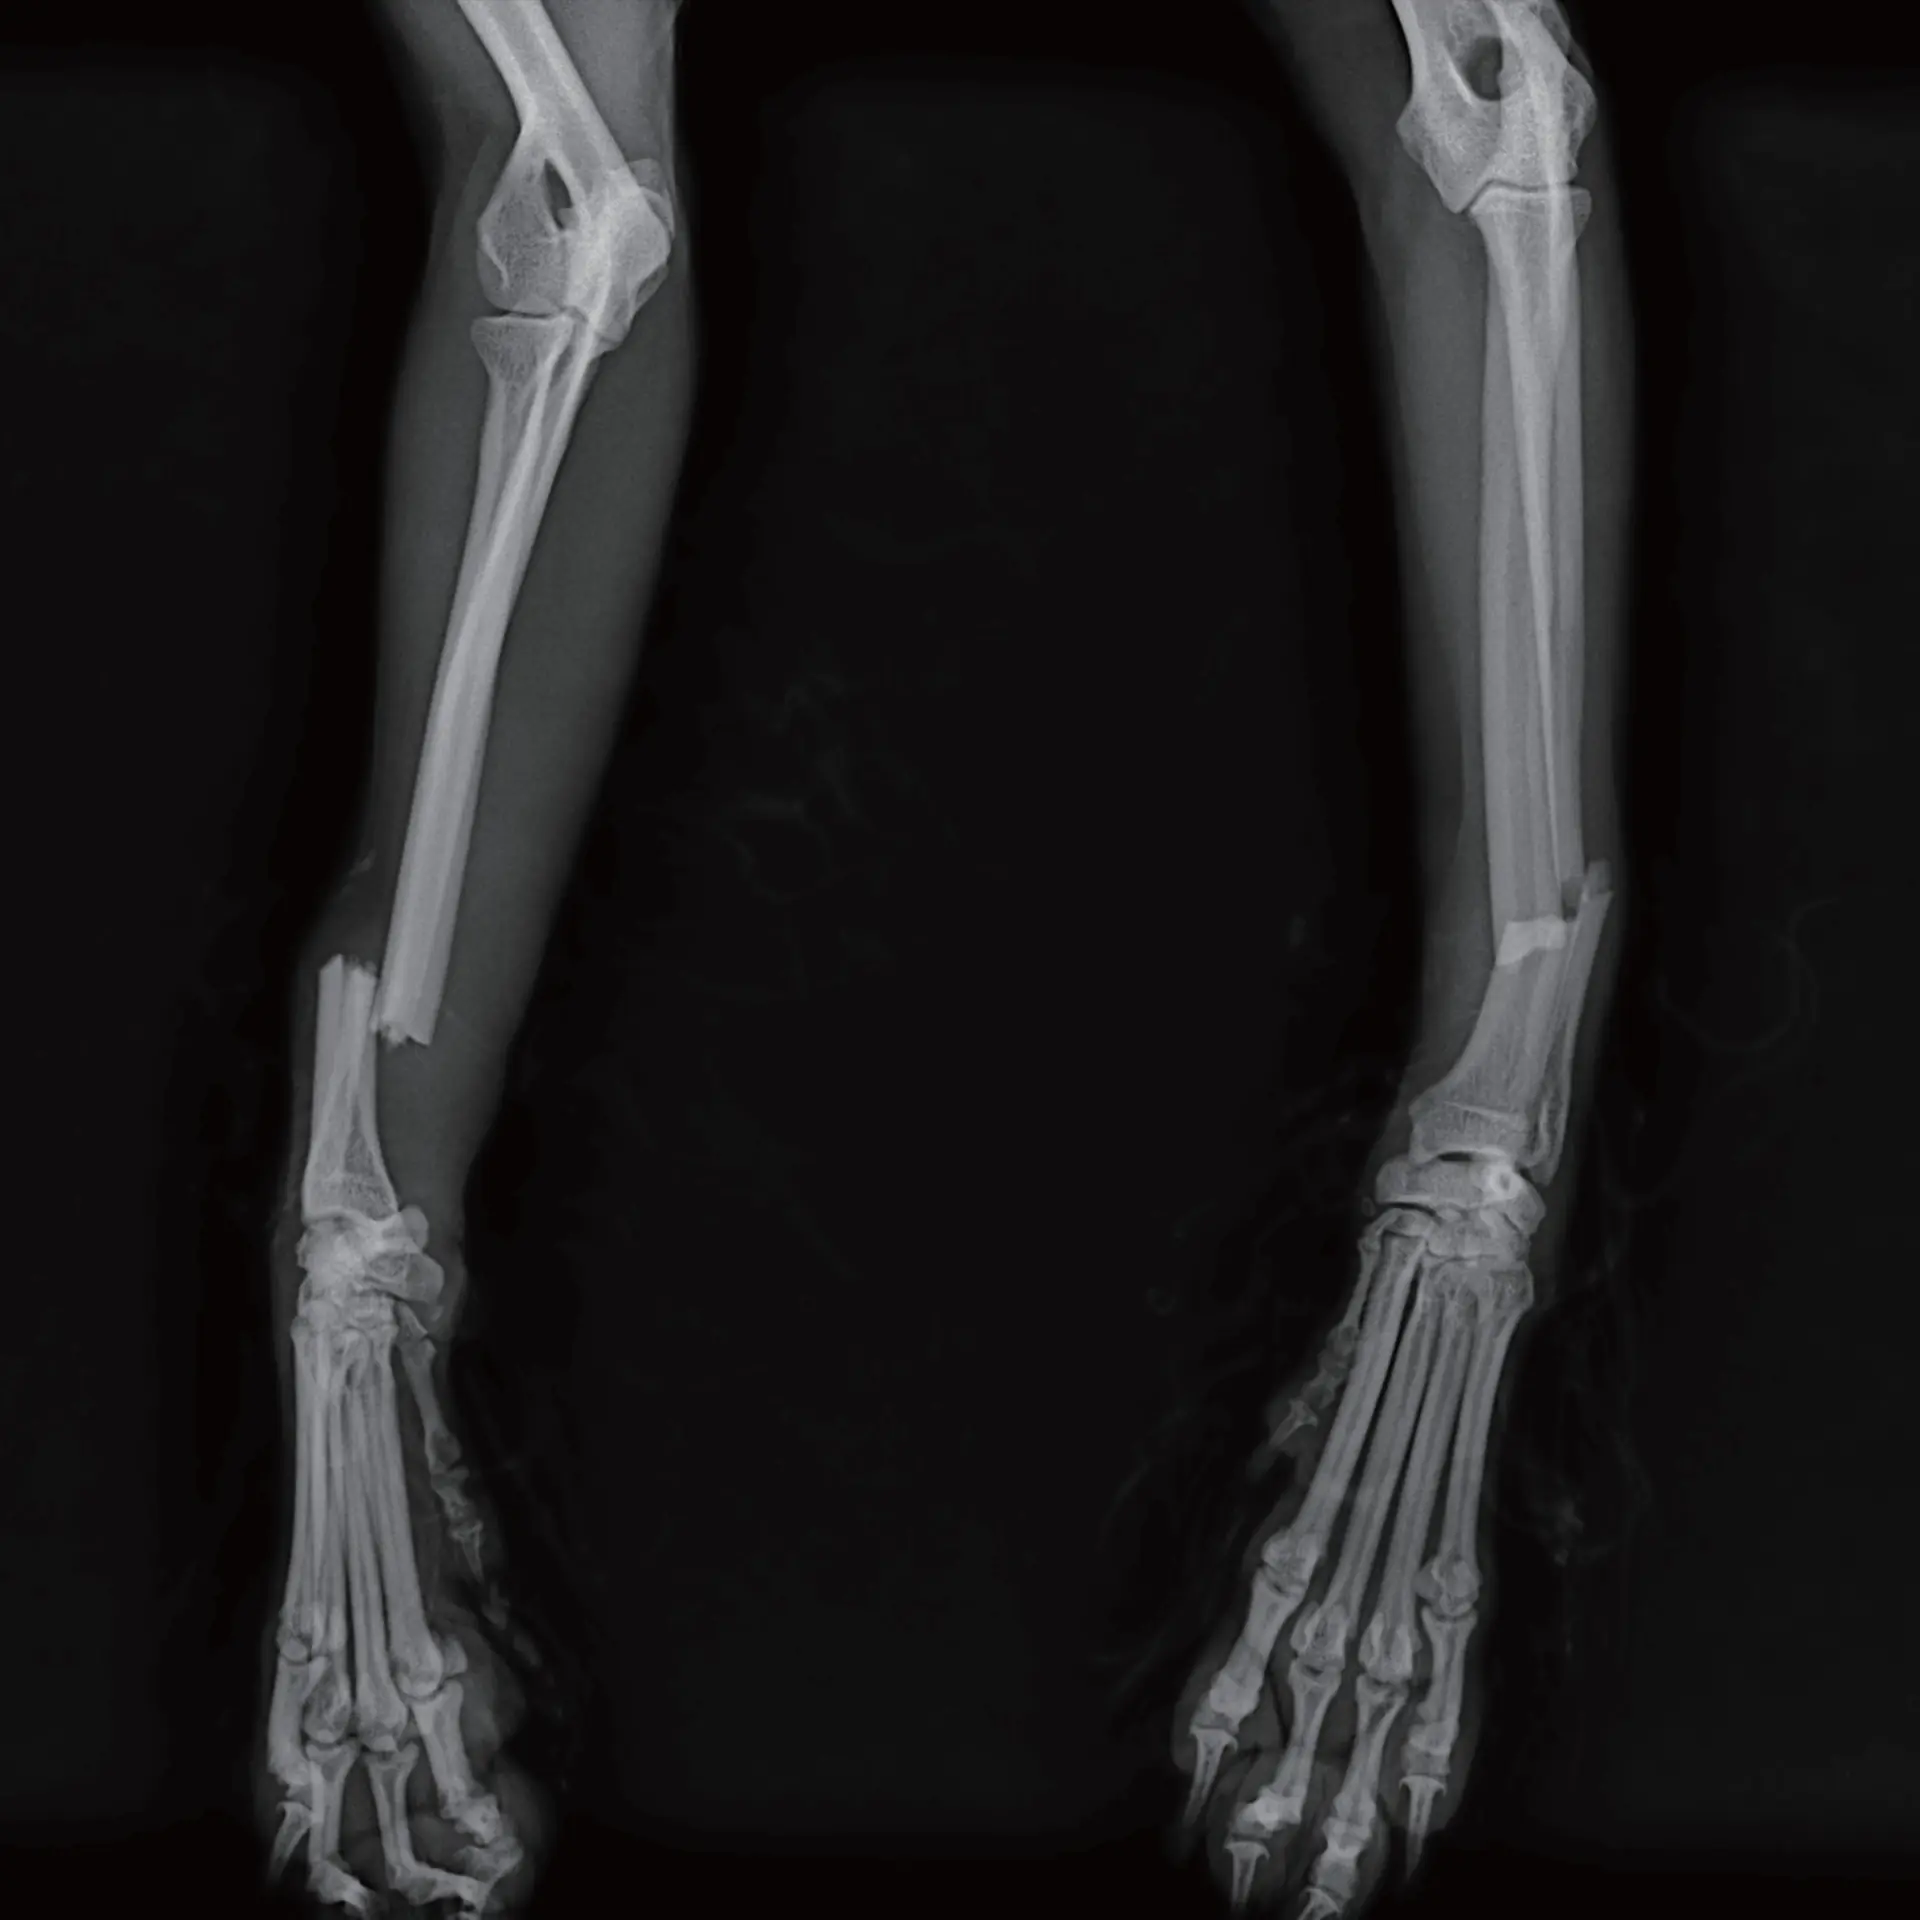

Ortopedik Görüntüleme

Kırık sonrası post-operatif inceleme